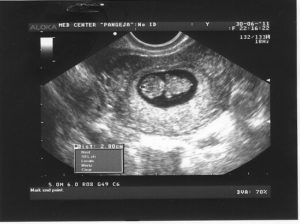

УЗИ

На протяжении беременности каждая женщина должна пройти три плановых УЗИ. Срок проведения плановых исследований:

- первое УЗИ назначается на срок от 10 до 12 недель;

- второе УЗИ проводят, когда срок беременности составит от 18 до 22 недель;

- третье УЗИ нужно будет пройти ближе к родам, когда срок составит от 33 до 35 недель.

Помимо плановых УЗИ могут быть назначены и дополнительные, если появятся показания.

Совет! Проведение УЗИ не оказывает отрицательного влияния на плод, поэтому будущие мамы не должны бояться, если врач рекомендует пройти дополнительное обследование.

Стоит ли делать УЗИ на 9 неделе? Ведь первое плановое обследование назначают не ранее 10 недели? Ответить на эти вопросы сможет только врач. Возможно, он перенесет УЗИ на неделю, когда срок беременности достигнет 10 недель. А может быть порекомендует не ждать 10 недели, а пройти обследование немедленно. Как правило, УЗИ ранее 10 недели назначают:

- при подозрении на внематочную беременность;

- для подтверждения или исключения многоплодной беременности;

- для выявления патологий плода, плаценты, матки;

- подозрение на то, что беременность перестала развиваться.

Если же особых показаний нет, то врач, как правило, рекомендует дождаться 10 недели и пройти плановое исследование. Но даже в том случае, если врач не советует ждать наступления 10 недели, будущая мать не должна пугаться.

Внеплановое исследование вполне может подтвердить, что с плод развивается нормально. То есть, оно нужно еще и для того, чтобы будущая мама перестала волноваться. Ведь нервозность матери отрицательно влияет на развитие плода.

Плод

Прошло всего около семи недель с того момента, когда соединились две клетки, но за это время плод заметно подрос. На этом сроке размер плода составляет примерно 2,5-3 см, а весит плод около 2 граммов.